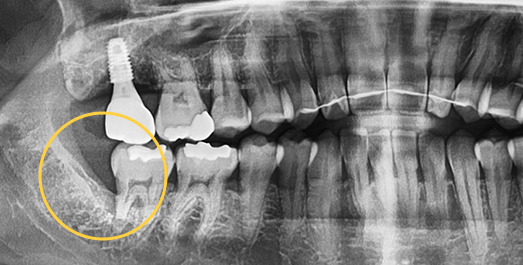

Extraction technique with nerve considerations

Using 3D CT, we evaluate the shape of the wisdom tooth, its roots, and surrounding nerves to support a safer extraction process.